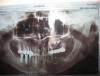

Лапушкина Опубликовано 26 февраля, 2013 Автор Поделиться Опубликовано 26 февраля, 2013 Вот панорамный снимок. Прикрепляю к этому сообщению.спасибо! Ссылка на комментарий